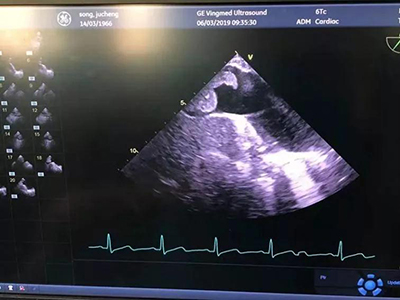

图为术中经食道超声检查

整台手术有条不紊、一气呵成。麻醉成功后,超声诊疗科主任郭文彬和麻醉科主治医师王旭、常媛,经食道超声检查再次确认了癌栓的上缘位置,决定采用第一套方案,即暂不采用体外循环。心外科副主任医师张文龙、胸外科副主任医师陈钢在台下随时准备。泌尿外科专家团队与肝胆外科专家密切配合,成功完成右侧肾根治性切除并下腔静脉癌栓取除术。整台手术历时80分钟,出血约150ml,取得了圆满成功。

本台手术的重要特点之一是术中在阻断近心房入口处的下腔静脉时由经食道超声实时检测,大大减少了钳夹下腔静脉时癌栓脱落的风险。手术中麻醉科医生进行了经食道超声实时检测,在我院尚属首例。这一实时检测技术极大增加了手术的安全性,对是否选择采用体外循环的辅助具有指导意义,是值得推广的经验。该手术的成功实施表明山东省立医院治疗肾癌并下腔静脉癌栓病例的技术已达国内先进水平。